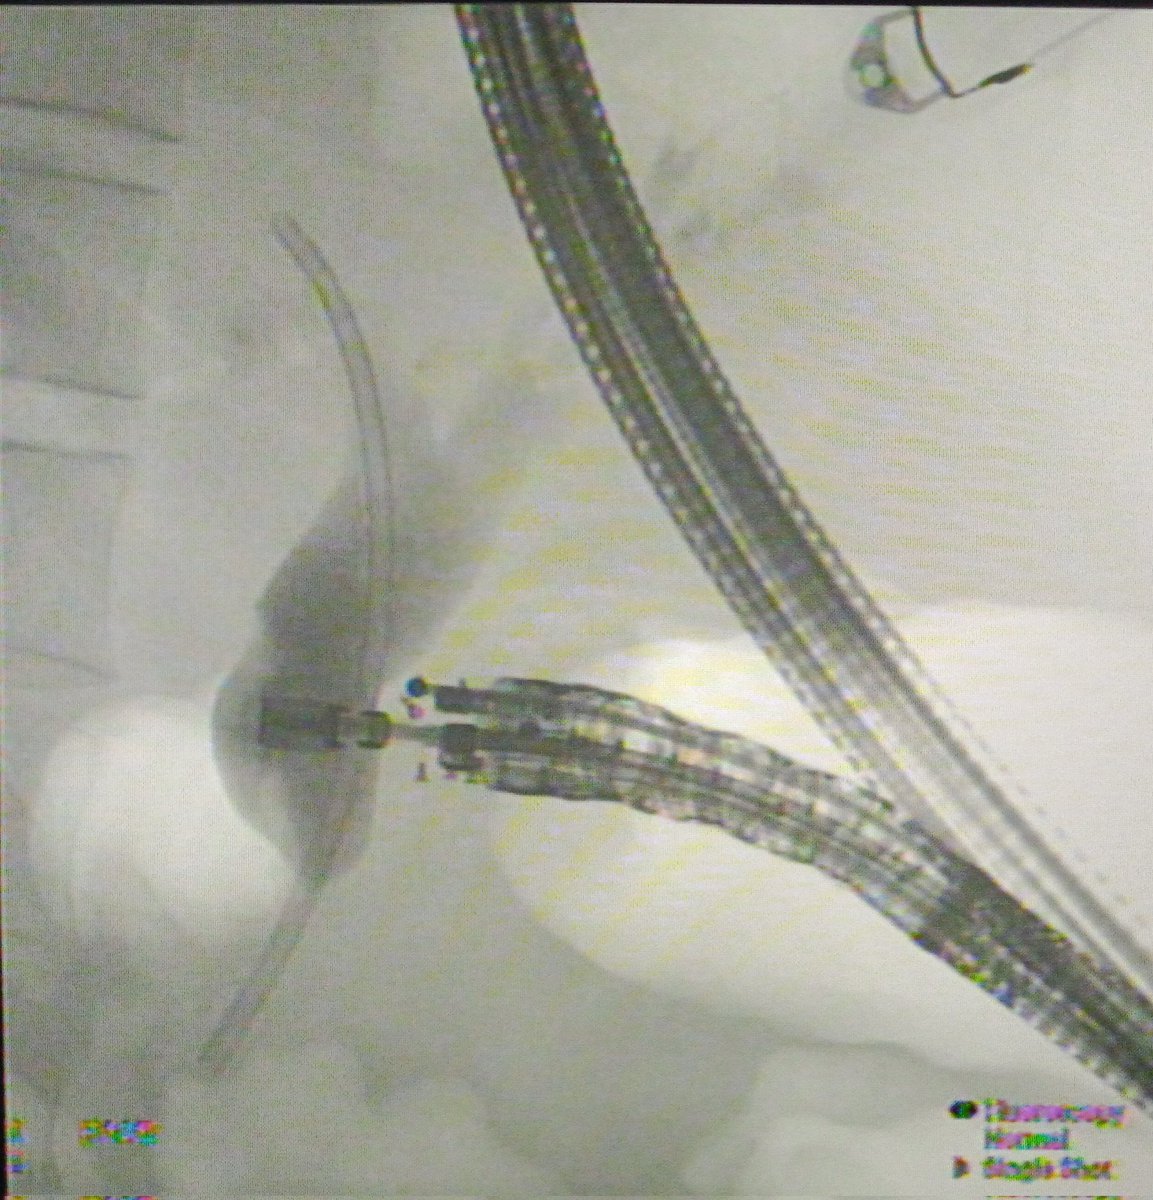

Yet another first for our centre and Rajasthan. First case of EUS guided Choledochoduodenostomy (CDS) done Department of Gastroenterology #AIIMSjodhpur @AIIMSJOfficial